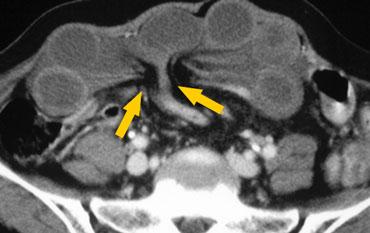

Hình ảnh CT của tắc ruột non dạng quai kín phụ thuộc vào hai yếu tố:

- chiều dài đoạn ruột tạo thành quai kín

- hướng của quai ruột so với mặt phẳng tạo ảnh

Nếu quai kín ngắn và nằm trong mặt phẳng tạo ảnh, chúng ta sẽ thấy quai ruột hình chữ U hoặc chữ C.

Tắc ruột dạng quai kín với các quai ruột giãn xếp theo hình nan hoa. Có dày thành ruột và phù nề mạc treo gợi ý thiếu máu cục bộ

Một hình ảnh quan trọng khác của tắc ruột dạng quai kín là các quai ruột non giãn xếp theo hình nan hoa với các mạch máu mạc treo hội tụ về một điểm trung tâm.

Hình ảnh này hầu như luôn do xoắn ruột non gây ra.

Các dấu hiệu thiếu máu cục bộ trong tắc ruột dạng quai kín tương tự như ở bệnh nhân thiếu máu mạc treo do các nguyên nhân khác:

- dày thành ruột

- phù nề mạc treo

- cổ trướng

- sự ngấm thuốc của thành ruột trong thiếu máu cục bộ có thể bình thường, tăng hoặc giảm.